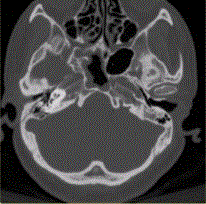

问题 患者男,20岁,外伤后右耳听力下降伴面瘫7d。临床检查,右耳传导性耳聋,发现脑脊液耳瘘。CT表现如下图。 对于颞骨骨折,最佳的影像学检查方法是

选项 A.X线平片 B.常规CT C.MRI D.HRCT E.CT增强检查

答案 D